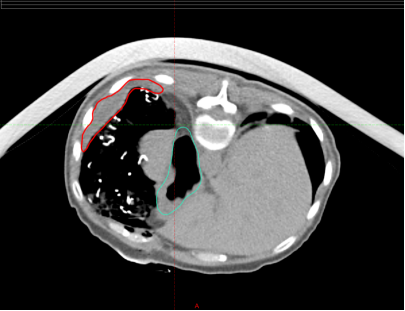

2)、重离子特色创新治疗技术:腹盆腔肿瘤瘤体与危及器官间手术置入隔离物的重离子放疗技术

重离子放疗是全球公认的尖端肿瘤放射治疗技术,尤其适用于外科手术、常规化疗及传统放疗无效或易复发的难治性肿瘤。临床实践中,重离子治疗因其具有独特的物理和生物学效应,能有效的杀灭各类肿瘤,但对于肿瘤和正常组织界限不清者,因担心正常组织的损伤,难以达到根治的治疗目的。

针对这部分难治性肿瘤,我科创新了整体解决方案,第一程给于基础治疗剂量,第二程通过手术放置隔离沙垫于瘤体与危及器官之间,当天完成定位、靶区勾画、计划制作、验证、复位及治疗,当天取出沙垫,使患者二程接受单次大剂量的根治性重离子放疗,确保患者安全的接受根治性大剂量放射治疗,疗效显著。整个过程放疗科、外科、麻醉科、放疗物理室、放疗技术室、影像科、运维人员、转运人员多学科配合,为患者保驾护航。

放置纱垫前 放置纱垫后